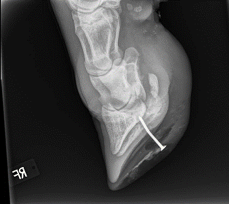

In one case a cow was presented to the VHC that had stepped on a nail, causing a severe lameness. (Figure 7) We completed radiographs to assess how far the nail was imbedded and how much internal damage was present. Soft tissue swelling was extensive. (Figures 8 and 9) There was also a lateral displacement of the third phalanx and a septic coffin joint. (Figure 9) Additionally, an abscess had exited at the coronary band. (Figure 10)

|   |   |   |   |

| Figure 7 | Figure 8 | Figure 9 | Figure 10 |